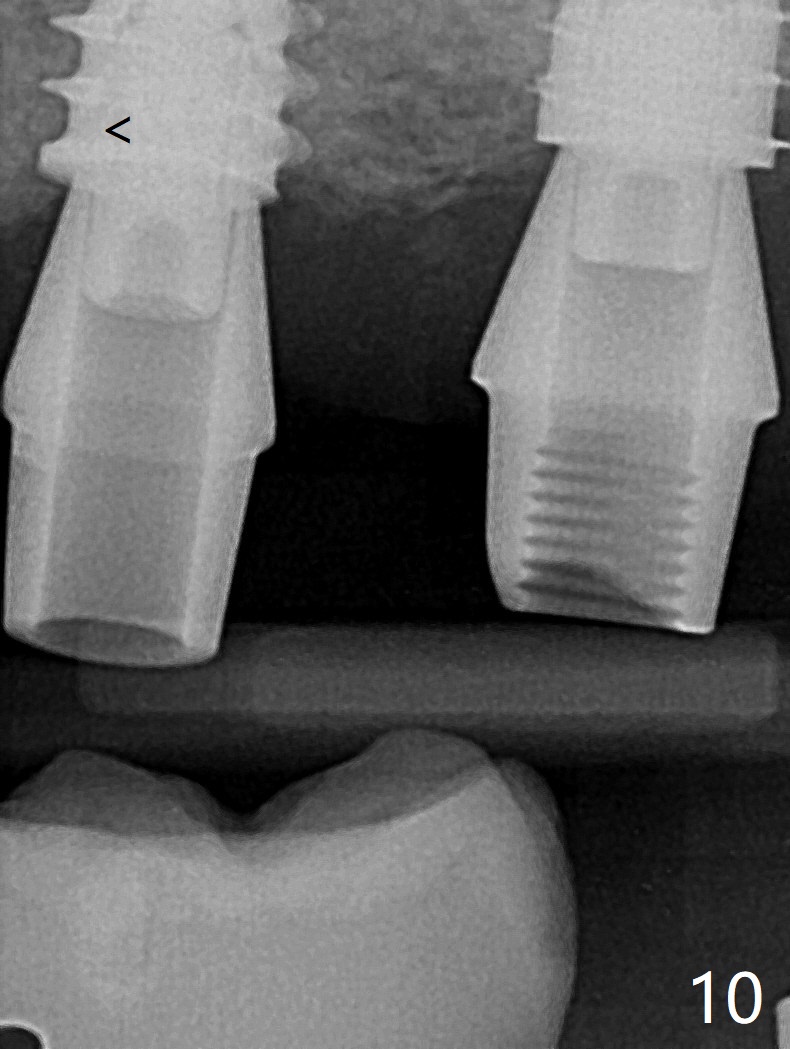

After finishing osteotomy with IS guide and Tatum Tapered tap 5x14 mm for 11 mm (gingival level) free hand, a 5x11 mm Tatum implant is placed at #18 with >15 Ncm (Fig.1). Bone harvested from the site of #18 will be used for #15 sinus lift (Fig.2 * as well as allograft). By the similar fashion, osteotomy at #15 is finished according to IS drill sequence except underdrilling (4.0x7.3 mm drill with 2 O-rings). Following use of DIO Sinus Approach Kit and placement of 2 pieces of PRF membrane and mixture of autogenous and allograft for sinus lift, a 4.5x11 mm IBS dummy implant is placed (Fig.2). With more allograft for sinus lift, a 5x9 mm implant is inserted with >35 Ncm (Fig.3). At #18 the implant 2.5 months postop (Fig.4) seems ok with removal of the cover screw and placement of a healing cuff. The implant at #15 appears osteointegrated with sinus lift 2.5 months postop (Fig.5 *). Half month later, the implant at #18 is tender associated with unipost placement. The healing abutment returns. A pair abutment (5.5x4(4) mm; 25 Ncm) is placed at #15. When the patient returns 7 months postop, BWs are taken to confirm that the abutment at #15 is fully seated, whereas that at #14 is not (Fig.6). A healing abutment is then placed at #14. Osteointegration seems to occur at #18; there is no tenderness when a 4.5x3 mm abutment is placed (Fig.7). Provisional crowns are fabricated at #15 and 18 for progressive loading. When the patient returns 14 months postop, a 5x4(4) mm hex abutment is placed at #14 with apparent gap between the implant and abutment (Fig.8 (PA) open arrow). In fact the gap seems to be absent more coronally as shown by bitewings (Fig.9,10 <). All of the 3 crowns are cemented in situ (Fig.11, 12) although the one at #14 is removed with the abutment for removal of residual cement. When the latter is re-torqued, the abutment remains completely seated (Fig.12). However, the implants at #15 and 18 appear to be placed distally with free-end guides (black lines).